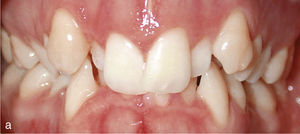

Con el sistema Invisalign se pueden tratar de forma muy eficaz las giroversiones y los apiñamientos del sector anterior. También permite realizar el enderezamiento de dientes en linguoversión. La figura 3a muestra un apiñamiento y dientes rotados en el sector anterior de la mandíbula, además de linguoversión de los premolares 34 y 35. Estos se pudieron enderezar con ayuda de un anclaje con ataches en los dientes 36 y 34. La conformación del sector anterior se llevó a cabo sin elementos de anclaje adicionales y con una reducción del esmalte interproximal. La figura 3b muestra el resultado una vez finalizado el tratamiento con Invisalign. A continuación se llevó a cabo un tratamiento conservador del margen de esmalte desgastado del diente 31.

Sector anterosuperior con dientes 11 y 21 en mesioversión y triángulo negro interdental (a). Se colocaron ataches rectangulares verticales en los dientes 11 y 21 y en los anteriores adyacentes. Resultado del tratamiento después de enderezar los dientes 11 y 21 y de cerrar el triángulo negro (b).